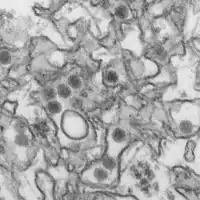

国际关注的突发公共卫生事件是由在2005年《国际卫生条例》下运作并由国际专家所组成的突发事件委员会宣布,[4]该委员会是在2002年至2003年SARS事件爆发后所成立的。[5]自2009年以来,共计有七次国际关注的突发公共卫生事件,[6]分别是:2009年H1N1流感大流行、2014年小兒麻痺疫情、2014年西非埃博拉疫情、2015年至2016年寨卡病毒疫情[7]、2018年至2019年刚果埃博拉疫情[8]、2019新型冠狀病毒疫情[9][10][11],以及于2022年7月23日宣布的2022年猴痘疫情。这些事件都是临时性的,需要每三个月进行一次复核。[2]

寨卡(2016年)

2016年2月1日,世界卫生组织第四次宣布了“国际关注的突发公共卫生事件”,以应对美洲地区出现的小头畸形和格林-巴利综合征疫情。当时怀疑这次疫情与正在进行的2015年至2016年寨卡病毒疫情有关。[32]后来的研究和证据消除了这些担忧。

2016年4月,世界卫生组织表示“科学界已认可将寨卡病毒为小头畸形和格林-巴利综合征的病因”。[33]这是首次针对蚊媒传染病的“国际关注的突发公共卫生事件”。[15]